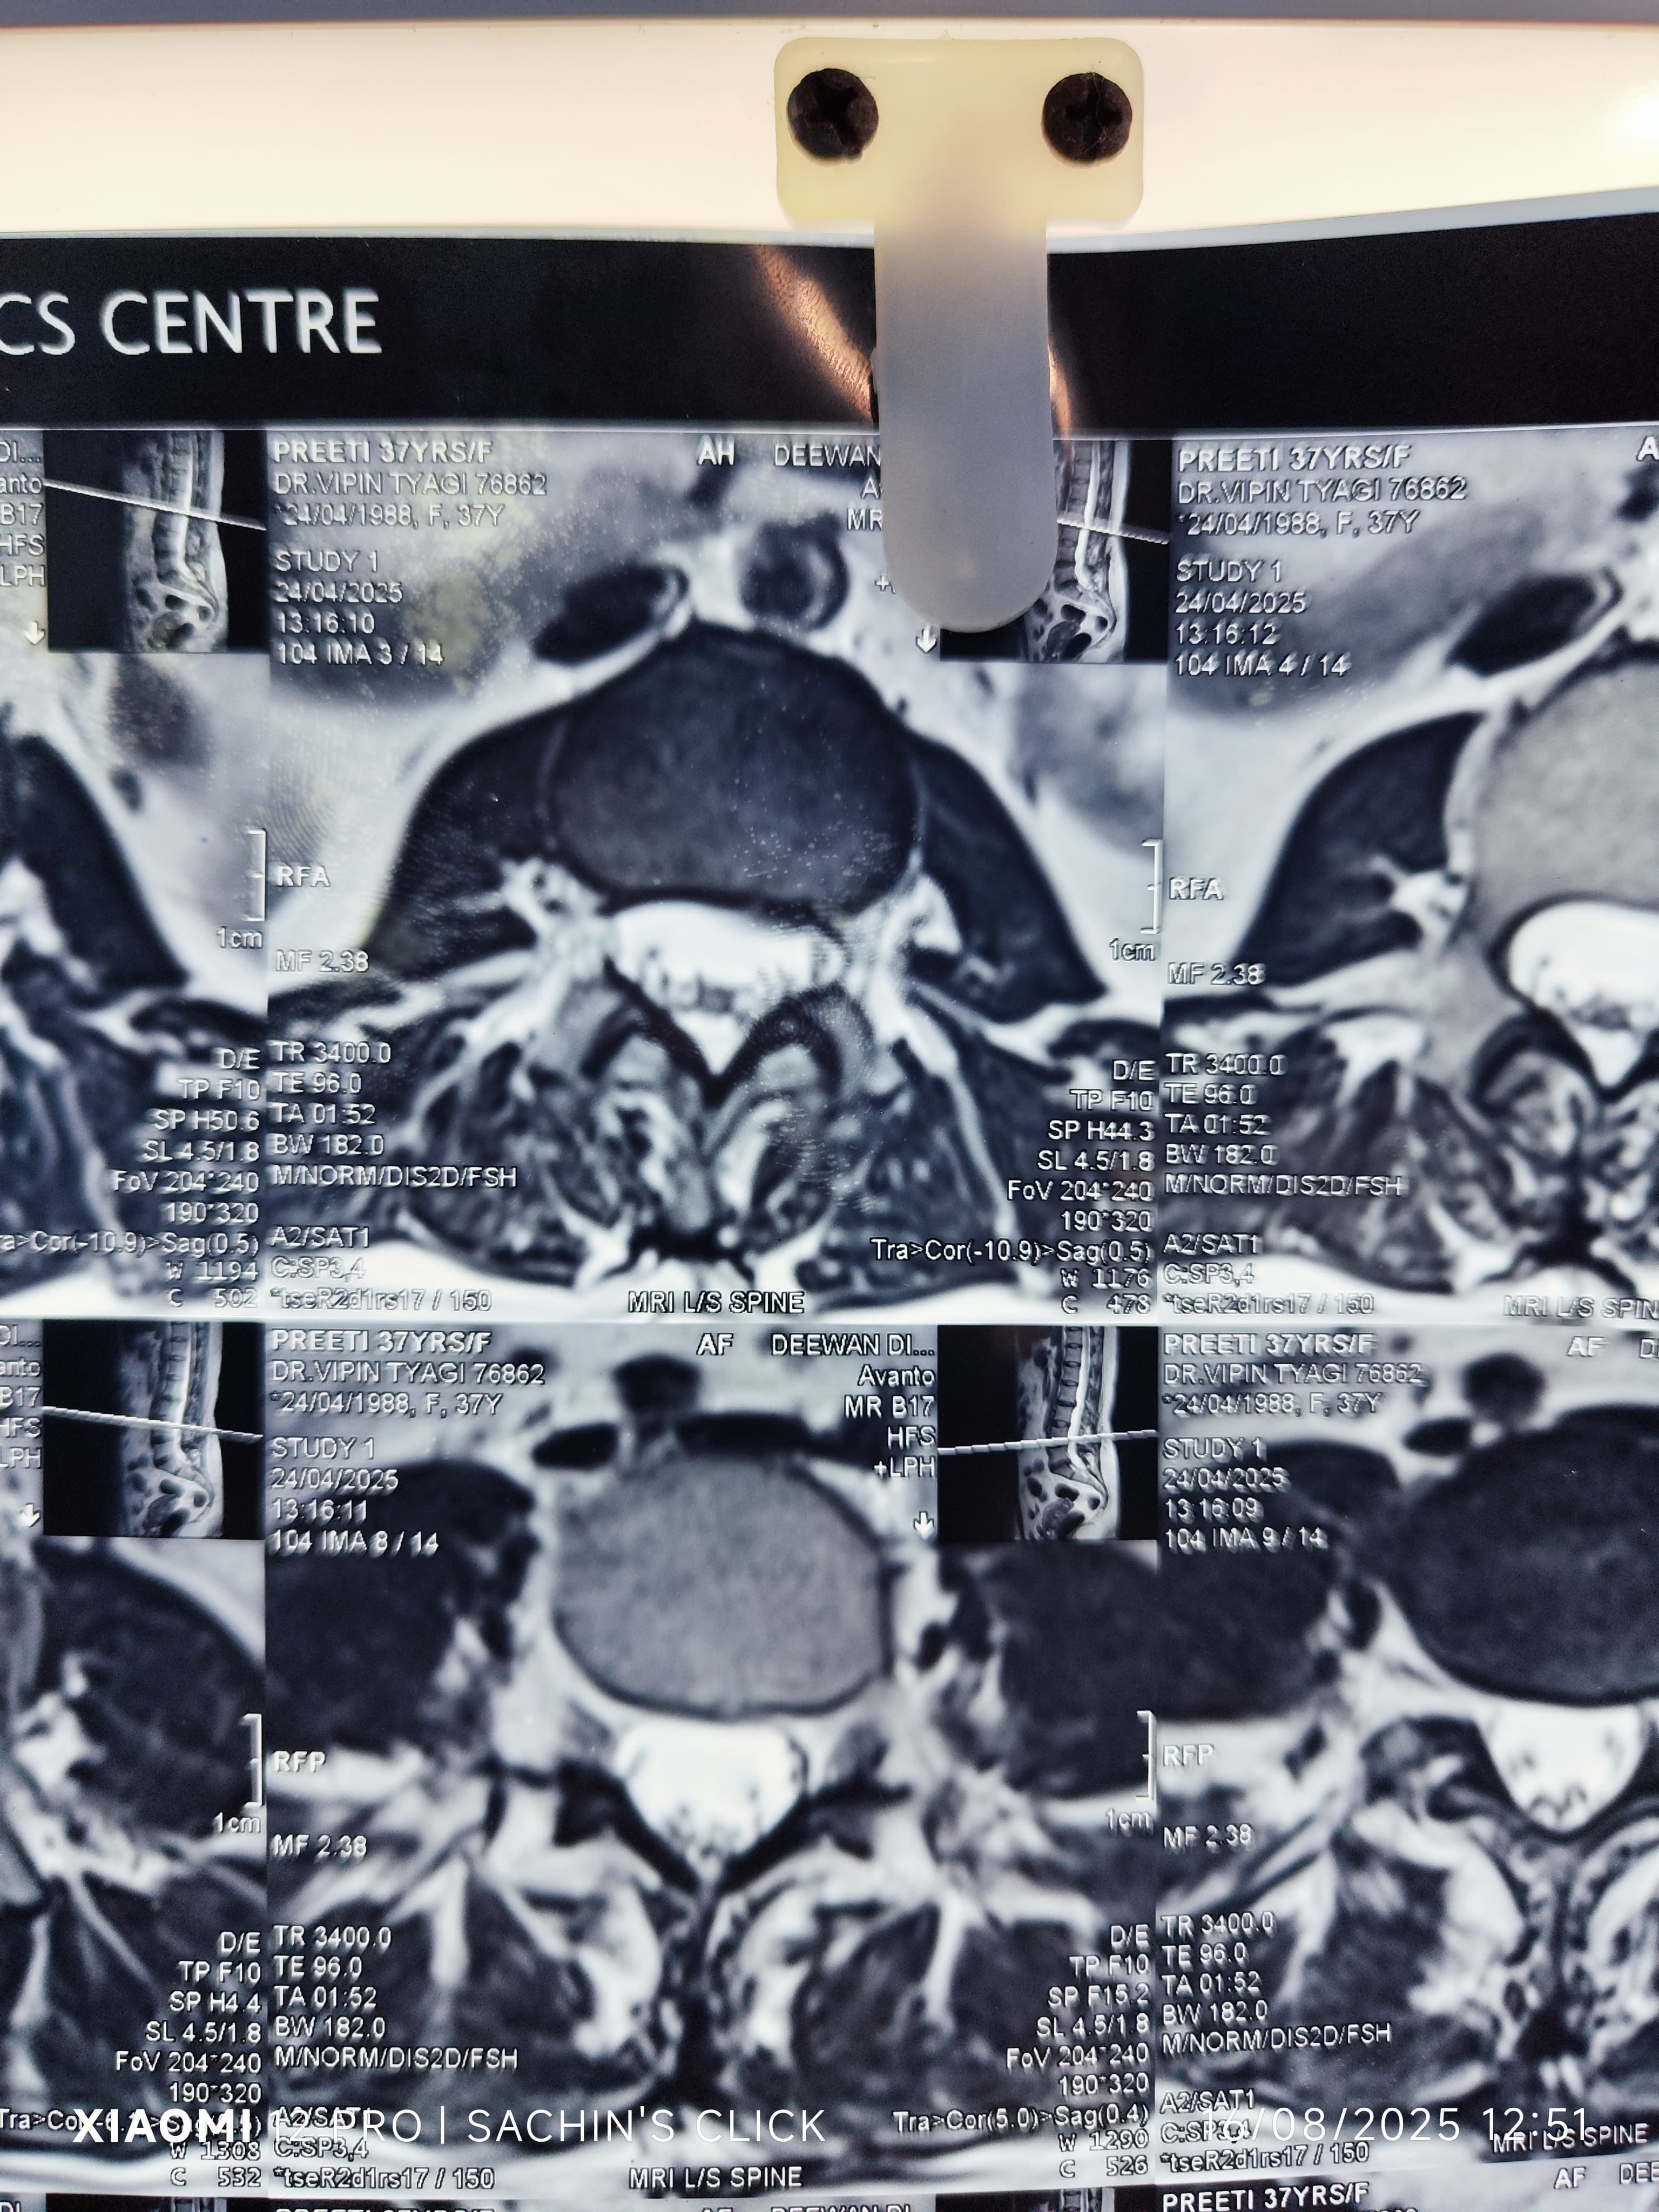

Glimpses of Advance Pain Care

Step inside our clinic and see our commitment to a healing environment and advanced care.